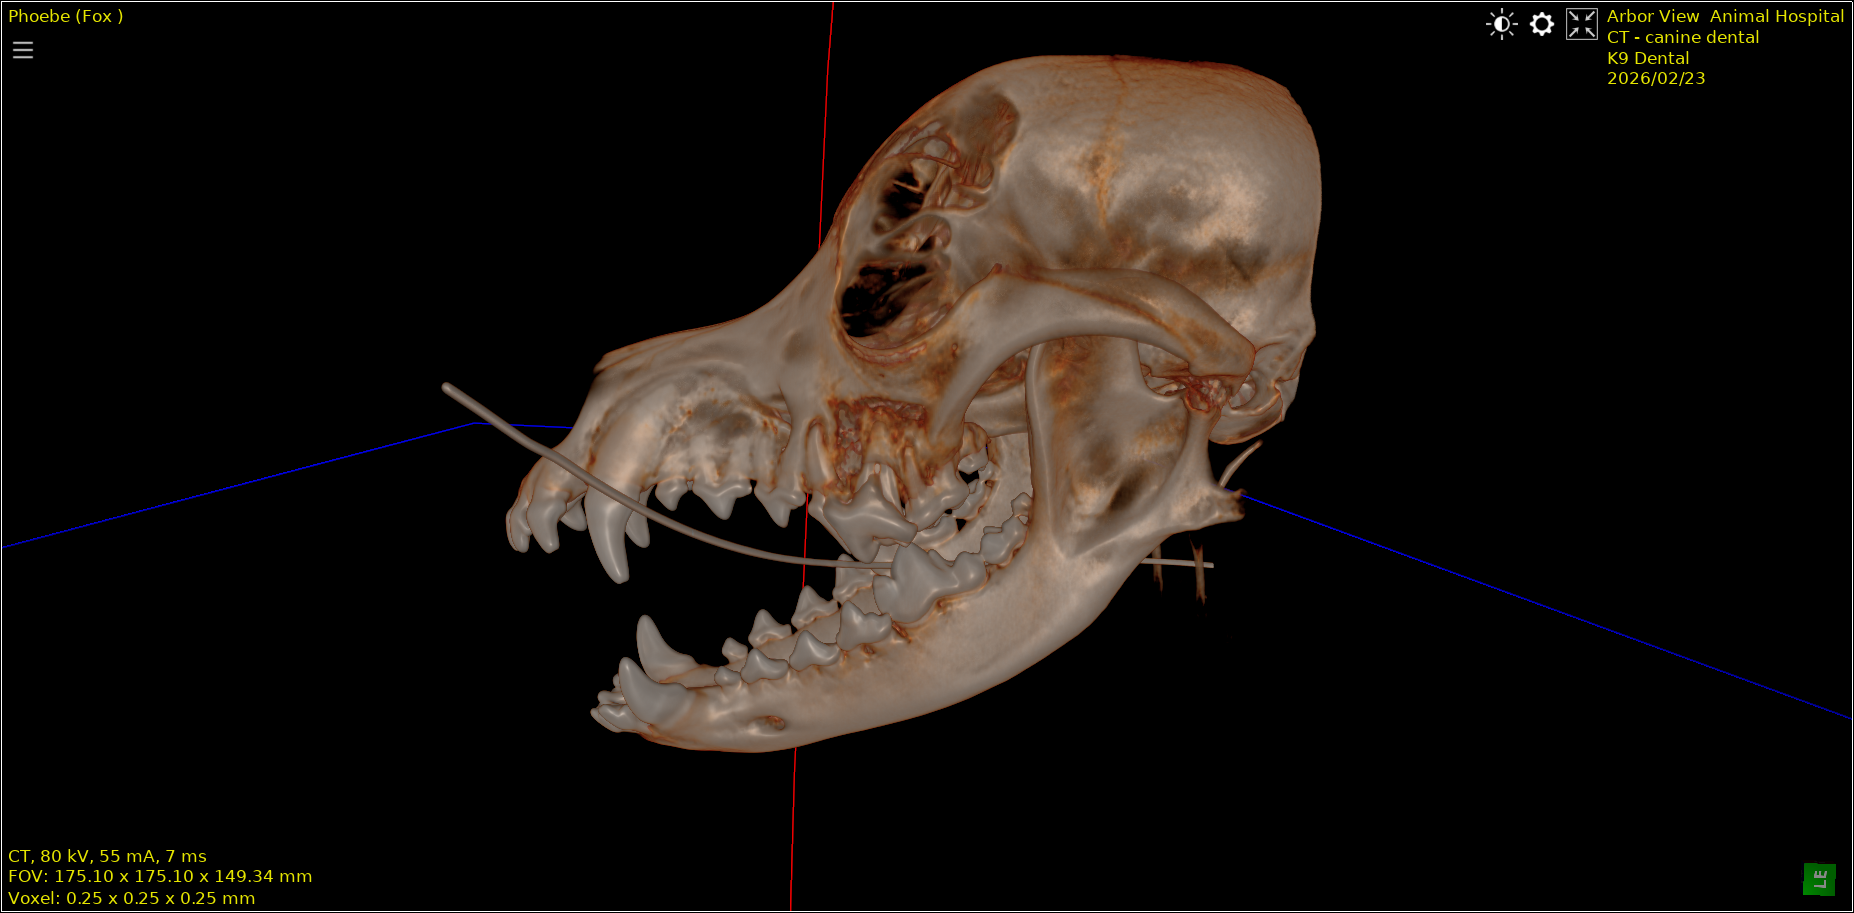

Advanced Diagnostics for Dental Disease

At Arbor View Animal Hospital we use advanced imaging tools to evaluate the health of teeth, roots, and surrounding bone structures.

Our hospital is one of the few veterinary clincs in Northwest Indiana offering CT imaging to evaluate complex dental disease.

Our diagnostic tools include:

• CT imaging

• Dental radiographs (X-rays)

• Comprehensive oral examination under anesthesia

Advanced imaging allows veterinarians to identify:

• tooth root infections

• bone loss around teeth

• jaw fractures

• impacted teeth

• oral tumors

These conditions are often impossible to diagnose without imaging.